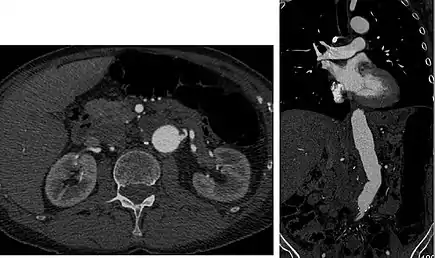

Early arterial phase (CT angiography)

CT angiography (CTA) is highly effective for evaluation of the arterial system, and has largely replaced conventional angiography due to the lower risk profile and ability to survey the entire abdomen. Images are acquired after a rapid bolus of intravenous contrast material (3-7 cc/s) during the arterial phase (15–35 seconds after injection) when the concentration of contrast material in the arterial system is high (figures 3). Images are usually acquired using narrow collimation (<1 mm) and can be retrospectively reconstructed using dedicated 3-dimensional workstations and software. CTA is commonly used in the head and chest in the evaluation of pulmonary emboli, aneurysms, vascular malformations, dissection, bleeding and ischemia. Indications for early arterial phase imaging include: evaluation of aneurysms or dissections (cerebral, aortic, etc.), hepatic, splanchnic or renal arterial anatomy, and arterial imaging in liver or kidney transplantation. Single phase arterial imaging is often used in the evaluation of trauma patients either a complete chest/abdomen/pelvis examination with arterial phase imaging of the chest and portal venous phase imaging of the abdomen/pelvis or just a portal venous phase of abdomen and pelvis depending on the mechanism and severity of the trauma. CTA is also commonly performed in the abdomen and pelvis for evaluating vascular malformations and in the evaluation of bleeding. Mesenteric ischemia can also be evaluated using CT angiography. CTA of the abdomen and pelvis is often performed in combination with a CTA for evaluating the extremity vasculature.